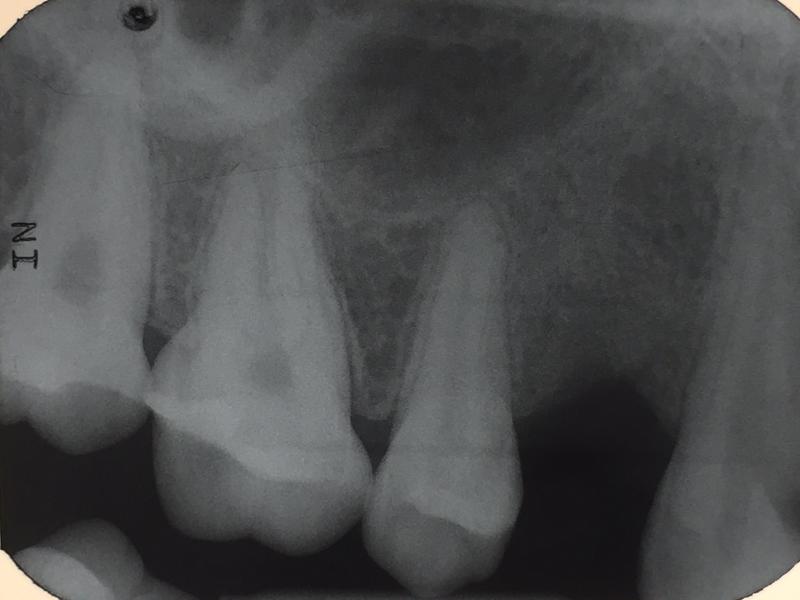

Nov2015 Zahn 14 Tiefe Füllung, entzündung, Wurzelentzündung,

Röntgen unauffällig, aber starke Schmerzen, etc

Ausfräsen, eitrig, Knochen verweicht